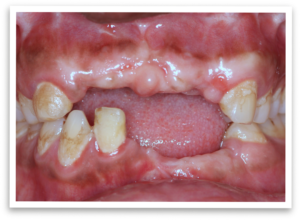

Life can take unexpected turns, and for this patient of ours, a serious accident left him with a fractured upper jaw, leading to missing front teeth. The initial medical treatment focused on mending the broken bone, but the missing teeth remained a constant source of insecurity for him. Unable to smile freely, the patient sought a solution to regain his confidence.

His journey to a new smile wasn’t straightforward. Dental scans (CBCT) revealed a critical challenge: thin teeth bone ridges in both his upper and lower jaw, making implant placement seem impossible. Even the slimmest implants wouldn’t provide a secure foundation for the replacement teeth.